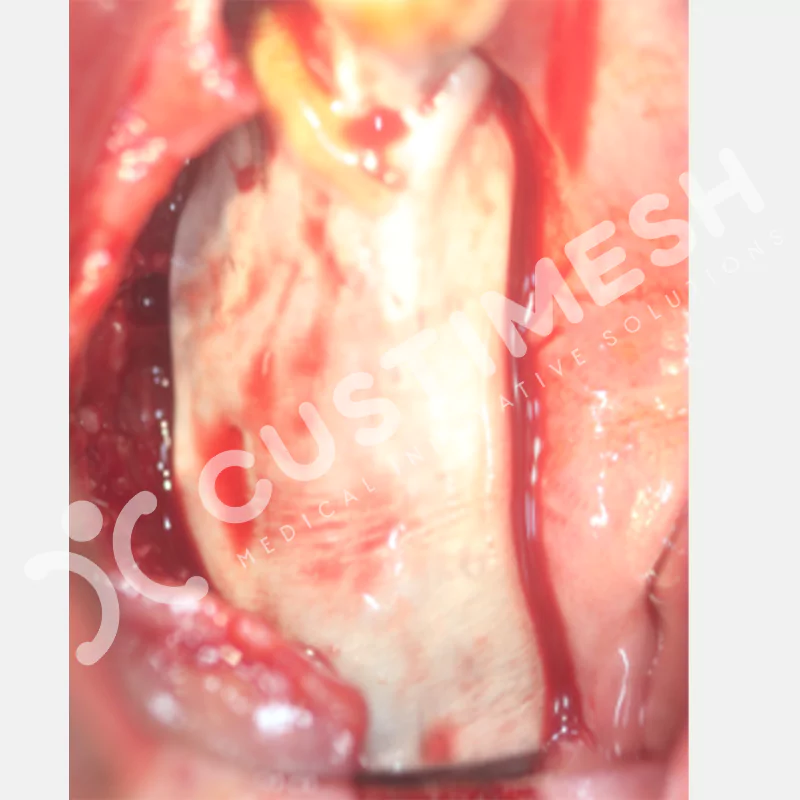

Dental implant uygulanamayan hastalarda kemik rejenerasyonunu sağlamak üzere geliştirilen kişiye özel titanyum mesh, kemik augmentasyon işlemlerinde greft materyalinin korunması ve yeni kemik oluşumunun desteklenmesi amacıyla kullanılan, hastanın kendi anatomisine tam uyumlu titanyum bir bariyer sistemidir.

Medikal sınıf titanyumdan, hastanın bilgisayarlı tomografi verileri kullanılarak CAD yazılımlarıyla tasarlanan ve 3D baskı teknolojisiyle üretilen bu yenilikçi çözüm, özellikle kompleks kemik defektlerinde standart meshlerin sağlayamadığı üstün mekanik stabilite ve mükemmel adaptasyon özellikleri sunar. Anatomik yapıya tam uyum sağlayarak greft materyalinin yerinde kalmasını garanti ederken, optimal vaskülerizasyonu destekleyerek kemik rejenerasyon sürecini hızlandırır.